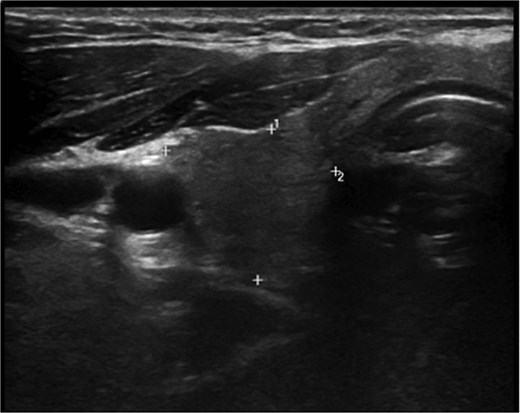

A 36-year-old gentleman presented to our clinic with a 1-month history of neck swelling, without any other complaints. The patient was medically and surgically free, had no family history or risk factors for thyroid cancer. Thyroid function tests revealed a normal thyroid-stimulating hormone (TSH) of 2.05 μIU/mL, which was within the normal range. The patient’s remaining laboratory results showed an elevated free thyroxine (T4) level of 26.7 pmol/L (reference range: 10.3–24.5 pmol/L). Corrected calcium was low at 2.03 mmol/L (reference range: 2.10–2.55 mmol/L), while magnesium, vitamin D, and albumin levels were within the normal range. Ultrasound of the neck, revealed a right lobe hypoechoic nodule 0.5 × 0.4 cm classified as TI-RADS 4. As well as a left lobe lesion measuring 2.3 × 1.7 cm, classified as TI-RADS 5 (Figs 1 and 2). Fine needle aspiration of the left lobe nodule confirmed the diagnosis of papillary thyroid carcinoma.